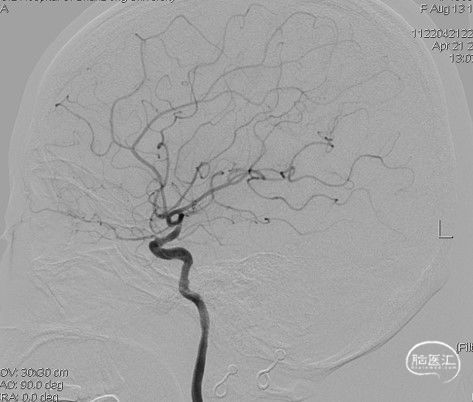

病人甲的影像资料:

造影:右侧颈内动脉末端变细,大脑前及大脑中自起始部闭塞,脑底少量烟雾血管形成,汇聚使R-MCA少量分支显影。

右侧颈内动脉侧位: